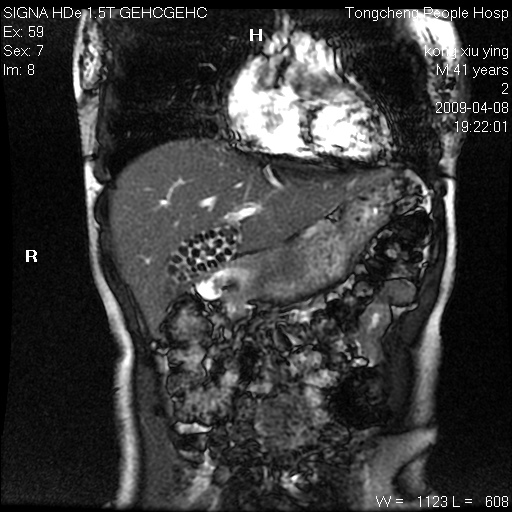

标题: CL1008:【经典】胆囊石榴籽样结石。

女,41岁。健康体检——彩超提示:胆囊显示不清。平素健康,无不适感。

腹部mr扫描及mrcp,图像如下: